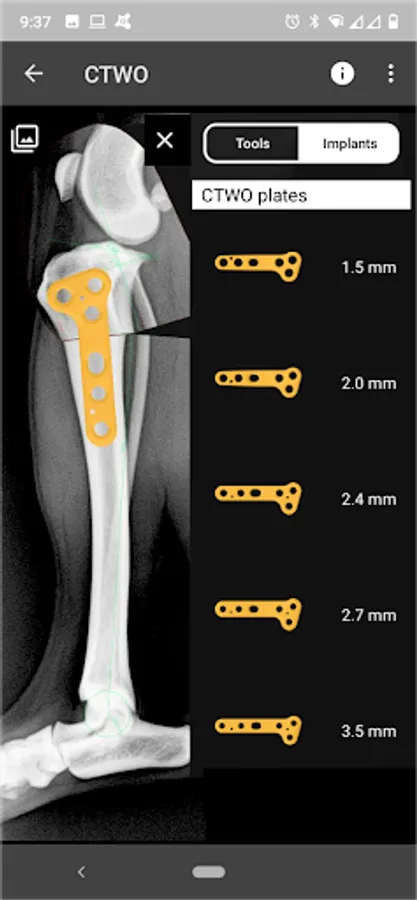

4. Catalogue of BETA Implants locking plates, in 2.0, 2.4, 2.7 and 3.5 sizes:

l) CTWO plates